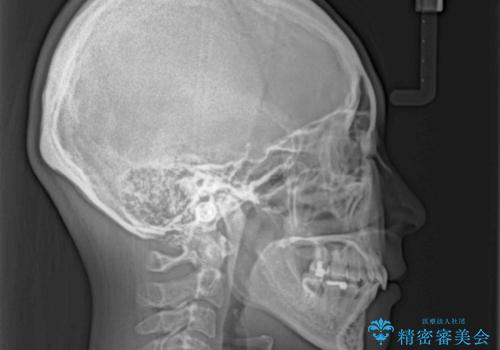

- 口元がひどく突出するくらいの上顎前突を気にして来院された患者様です。

舌の突出癖が顕著で、上顎歯列は完全なV字型となっている状態でした。

下顎歯列にも八重歯があり、上下左右の第一小臼歯4本を抜歯して、ワイヤー装置にて矯正治療を行うこととしました。

どこまで口元の突出感を改善できるのか不安でしたが、舌のトレーニングをしっかりと行ってくださり、我々も驚くほど劇的に改善することができました。